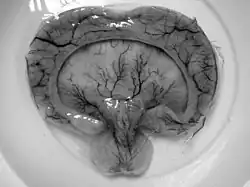

| Gross pathology specimen from a case of alobar holoprosencephaly, a clinical manifestation of Young–Madders syndrome first described as a new condition by doctors Young and Madders in 1987. |

Young–Madders syndrome is detectable from the fetal stage of development largely due to the distinctive consequences of holoprosencephaly, a spectrum of defects or malformations of the brain and face. Facial defects which may manifest in the eyes, nose, and upper lip, featuring cyclopia, anosmia, or in the growth of only a single central incisor, and severe overlapping of the bones of the skull.[2][3] Cardiac and in some cases pulmonary deformities are present.[2] Another signature deformity is bilateral polydactyly, and many patients also suffer from hypoplasia and genital deformities.[1]